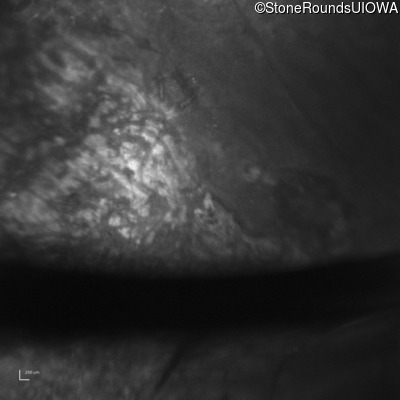

Optical Coherence Tomography - Right - 20/200 sc

Exemplar / OCT Stack